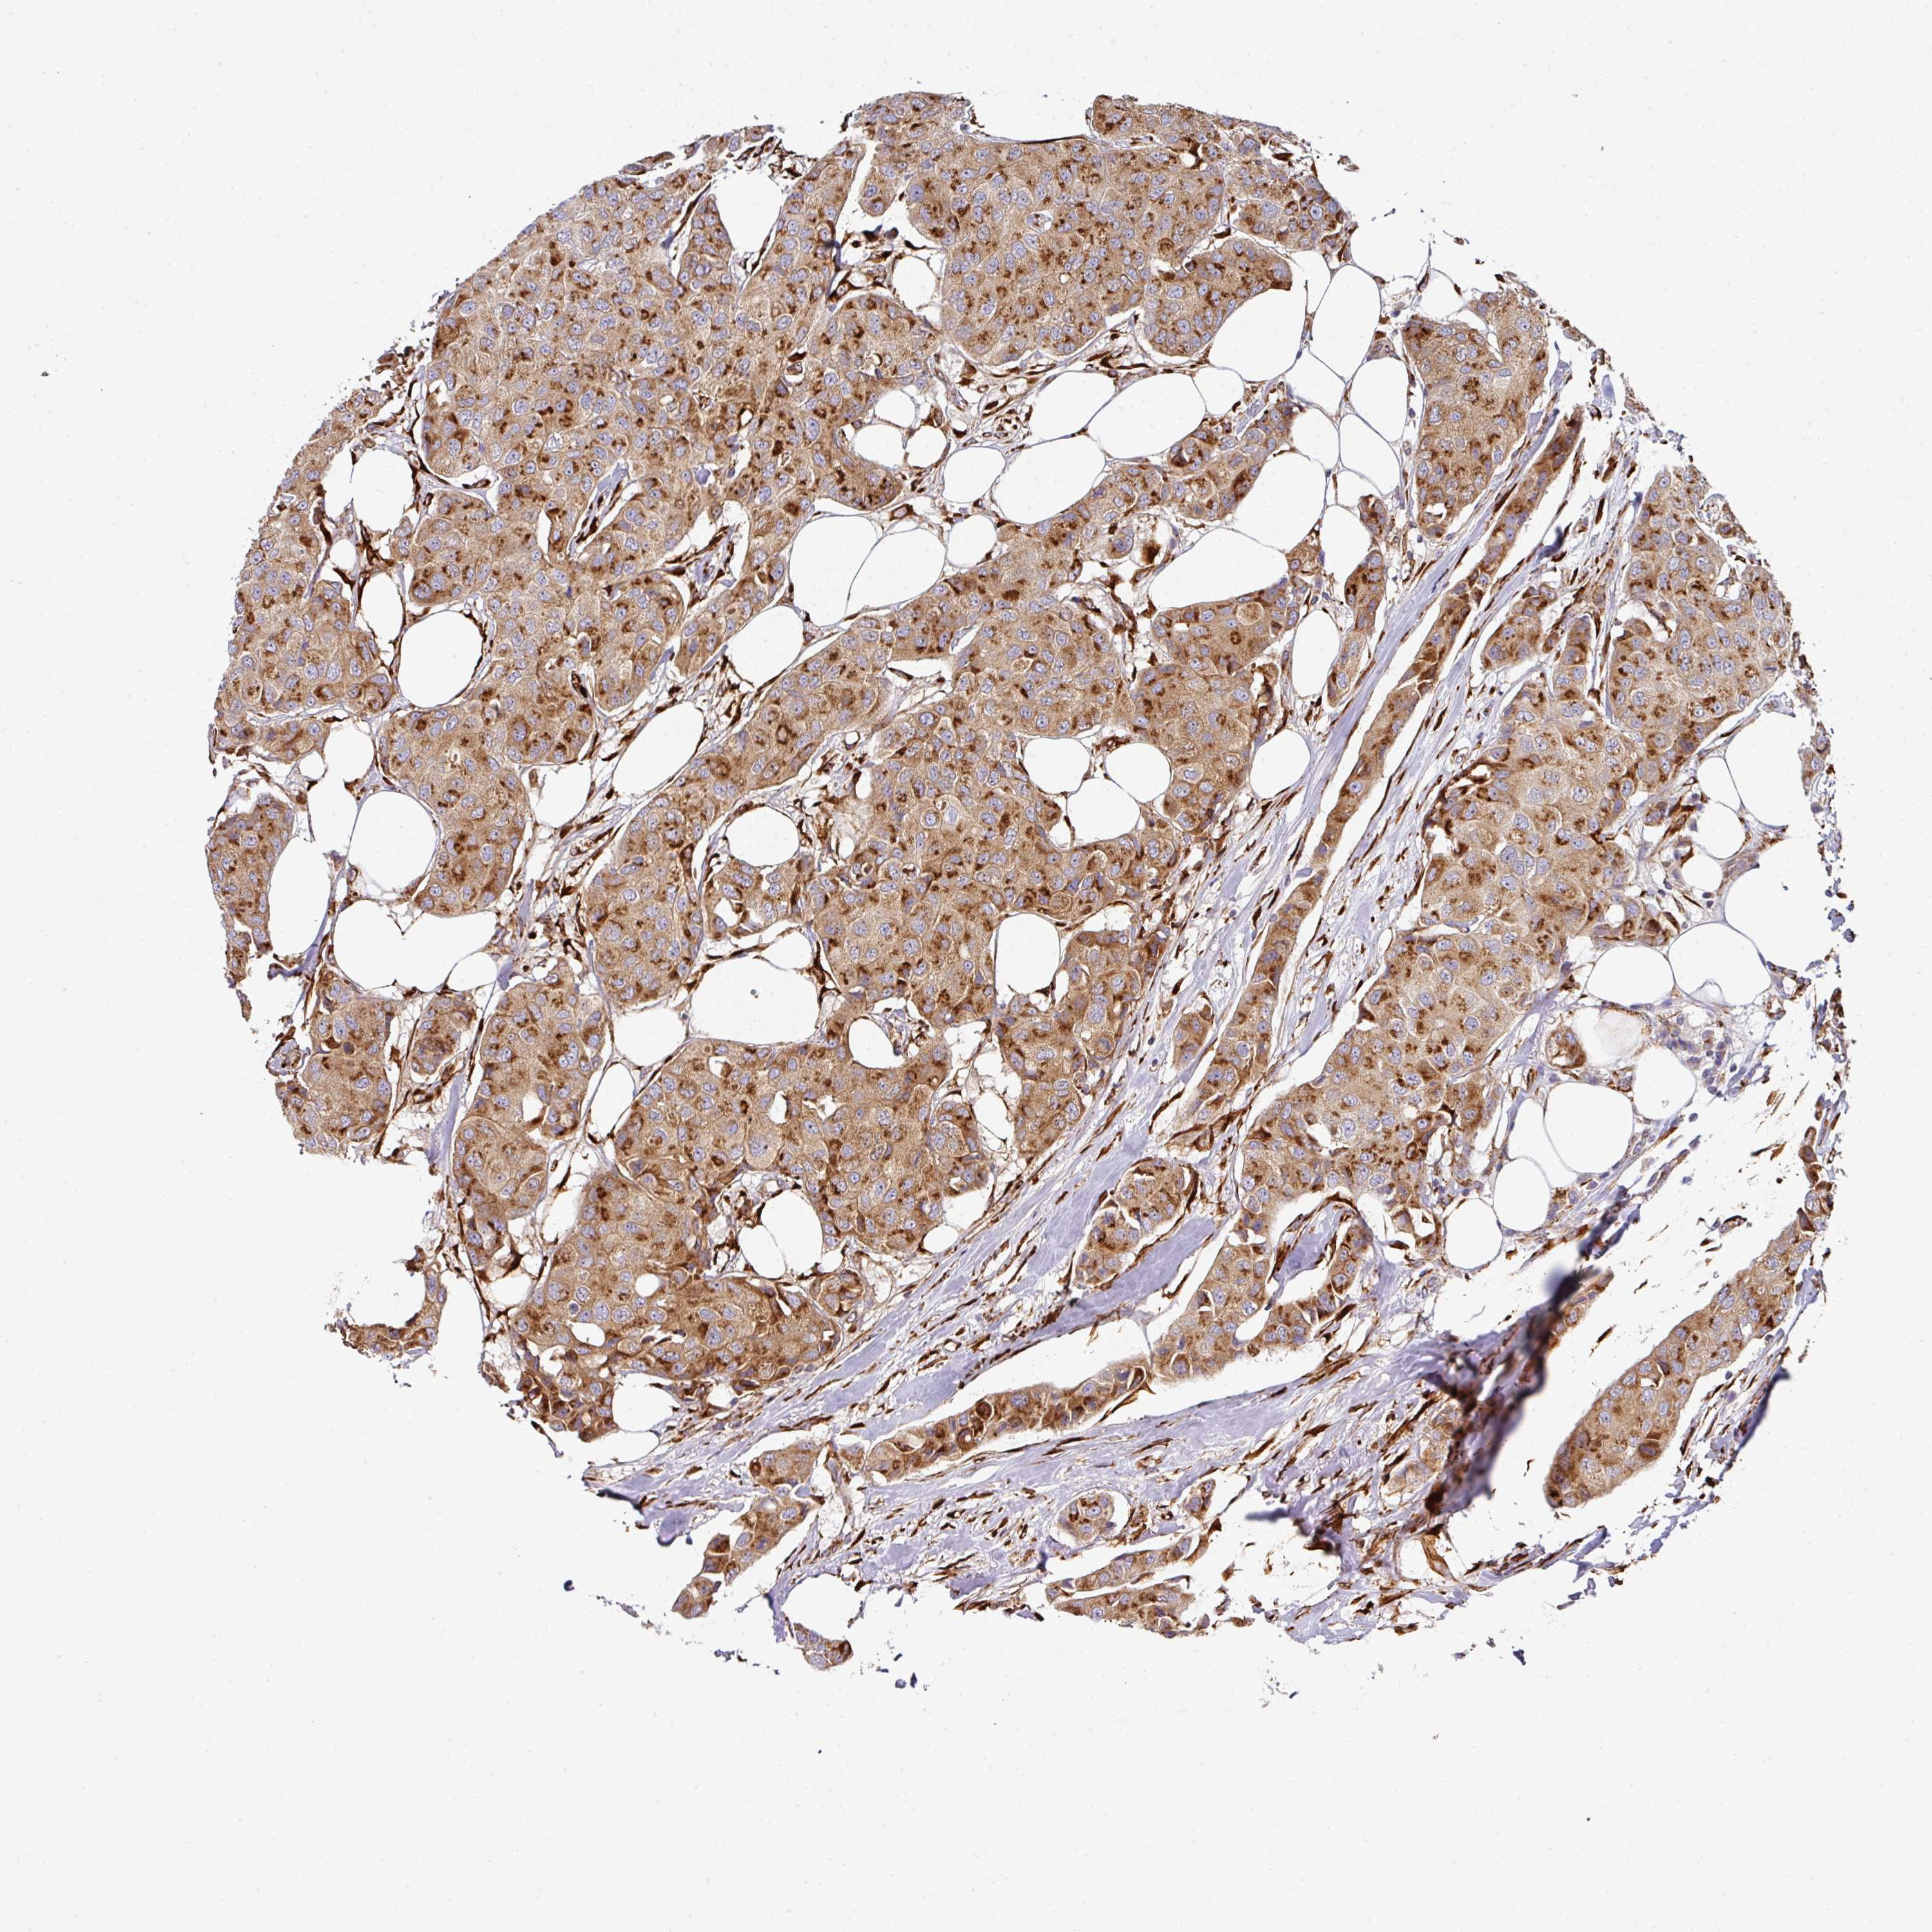

CANCER BREAST CANCER Show tissue menu

BRCA TCGA BRCA VALIDATION PROTEIN EXPRESSION

Breast cancer

Human cancer

Breast invasive carcinoma